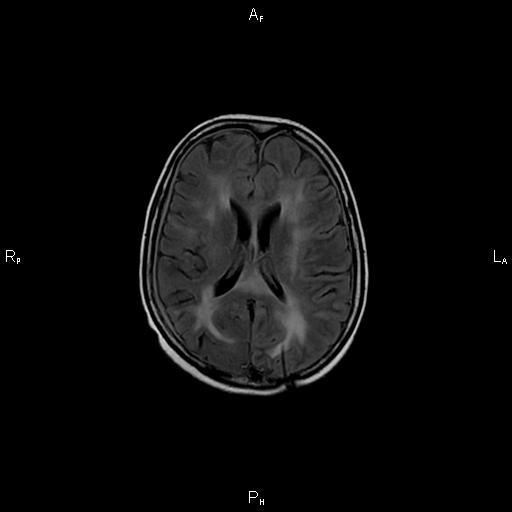

4. Рис. 1а

Тема

Тип Материалы исследования

Посмотреть (29KB)

Метаданные ▾

5. Рис. 1б

Посмотреть (28KB)